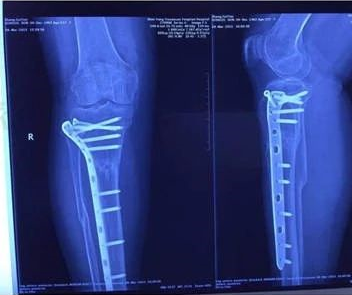

骨折延迟愈合

术后九个月未愈合 冲击波治疗后二个月

按骨折的部位和类型,经过治疗后,未能在平均时间内愈合,骨折断端仍未出现骨折连接,称为骨折延迟愈合。ESWT 具有成骨作用,在治疗骨折延迟愈合方面应用越来越广泛,治疗胫骨、跖骨、股骨等骨折延迟愈合时,总体有效率 70%~90%.